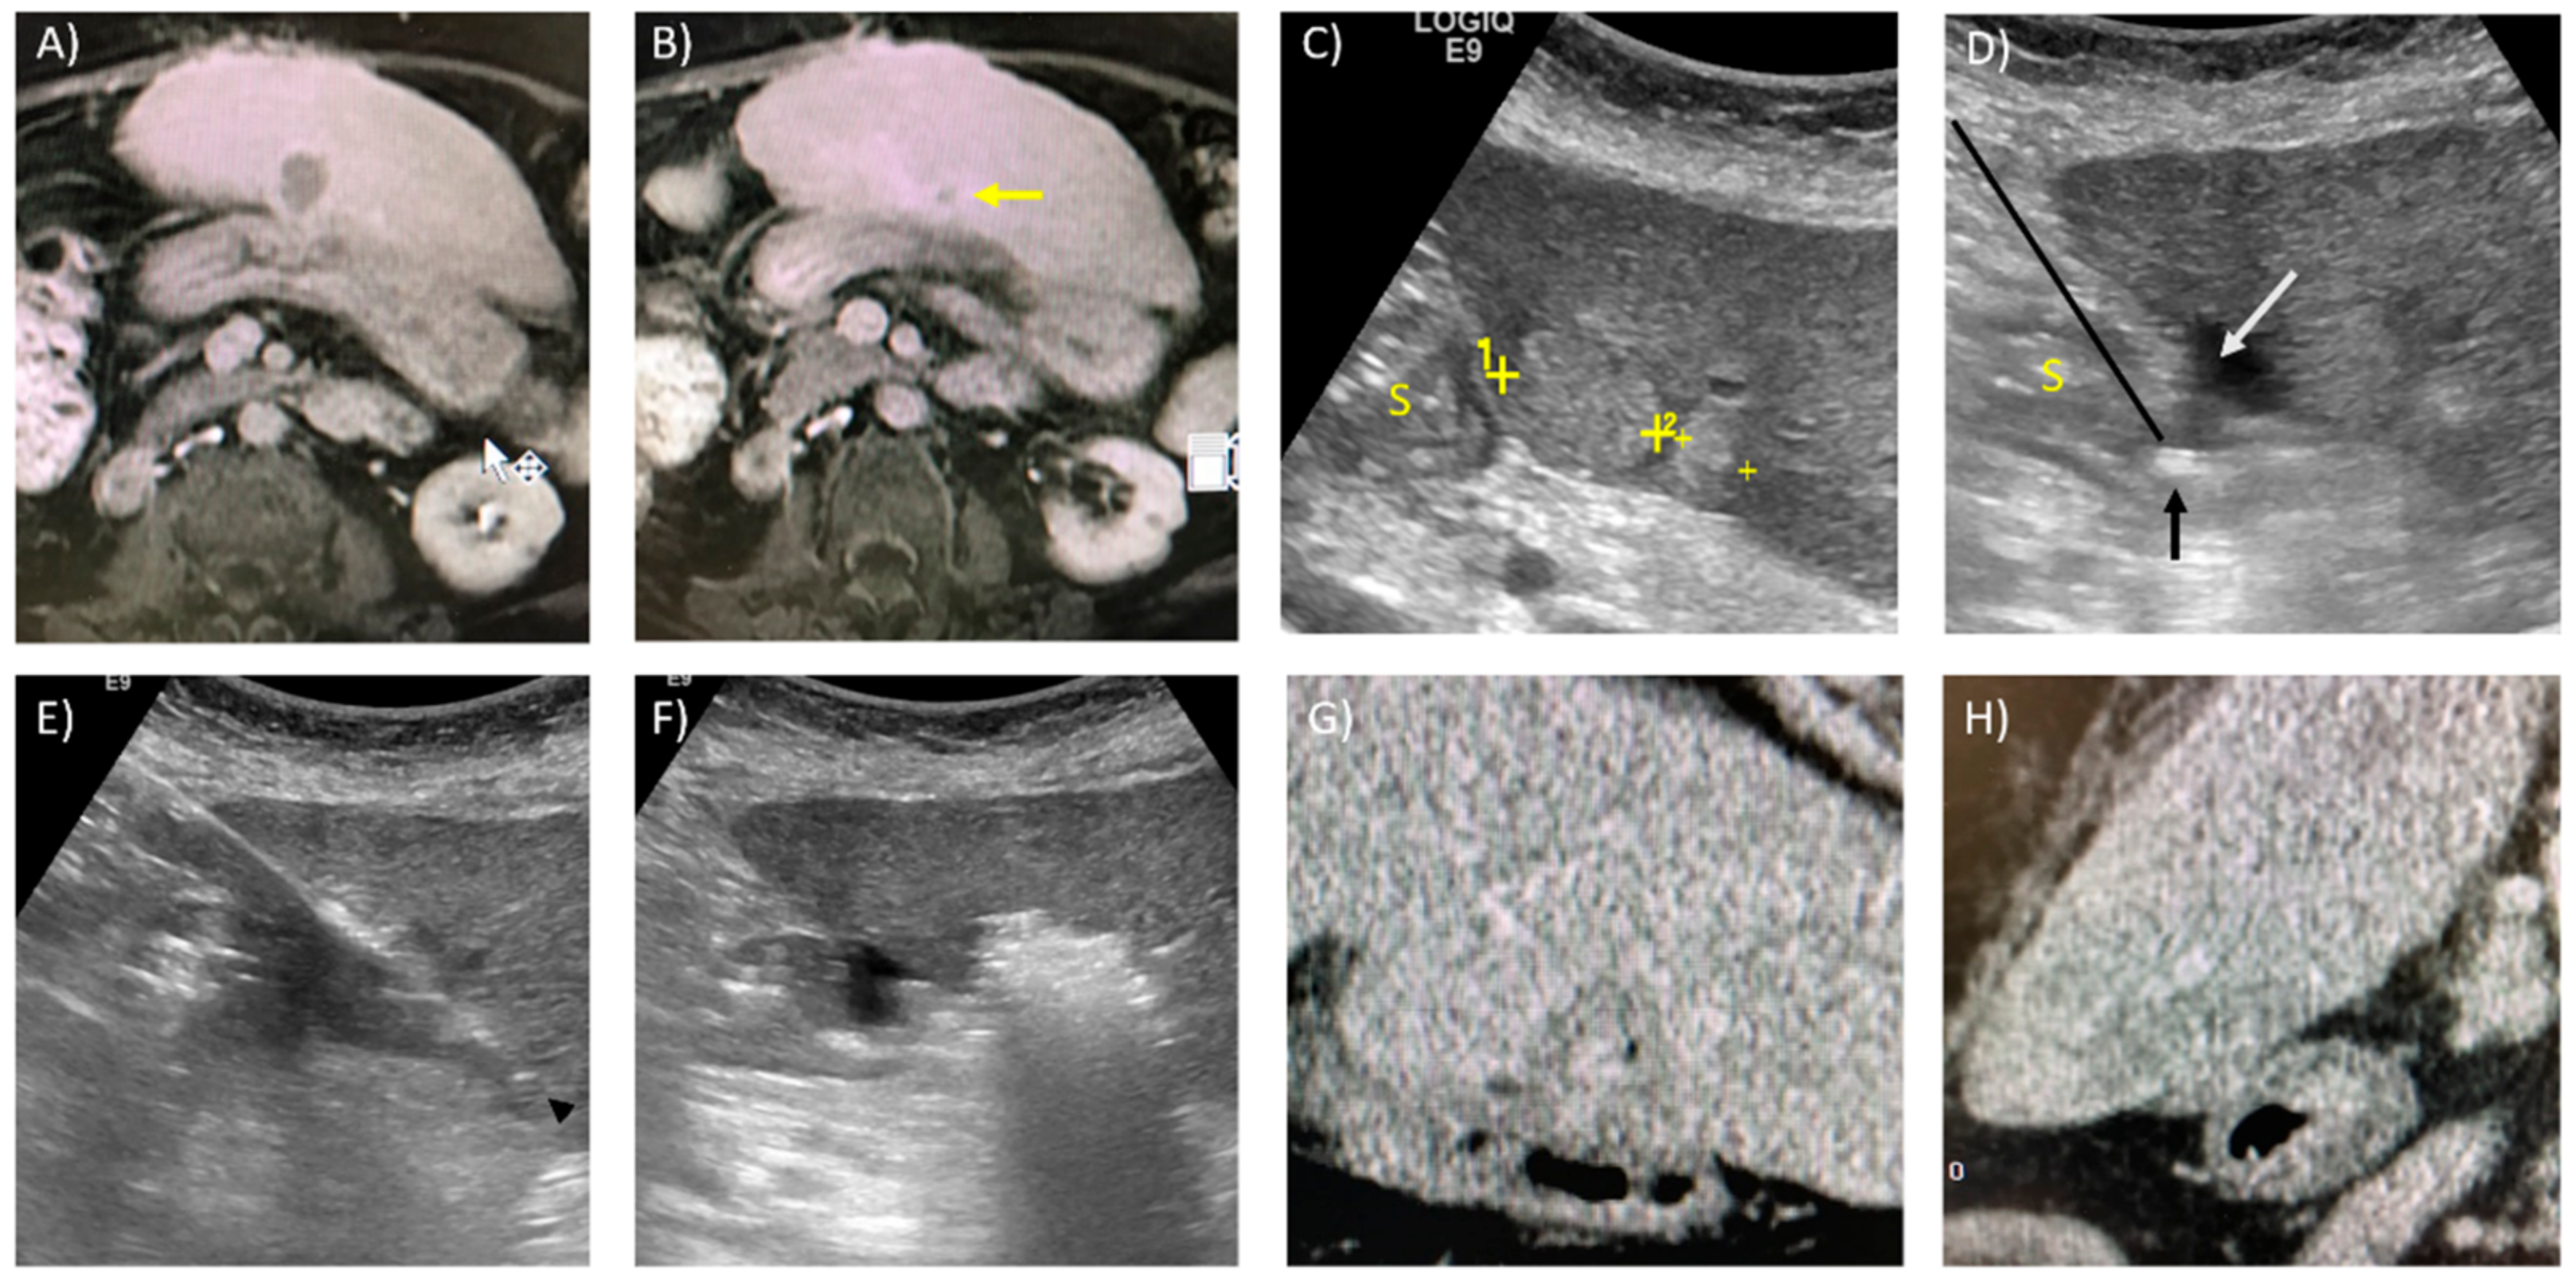

- Patel, P.A.; Ingram, L.; Wilson, I.D.; Breen, D.J. No-touch Wedge Ablation Technique of Microwave Ablation for the Treatment of Subcapsular Tumors in the Liver. J. Vasc. Interv. Radiol. 2013, 24, 1257–1262. [Google Scholar] [CrossRef]

- Rhim, H.; Lim, H.K. Radiofrequency ablation for hepatocellular carcinoma abutting the diaphragm: The value of artificial ascites. Abdom. Imaging 2008, 34, 371–380. [Google Scholar] [CrossRef]

- Rhim, H.; Lim, H.K.; Kim, Y.-S.; Choi, N. Percutaneous Radiofrequency Ablation with Artificial Ascites for Hepatocellular Carcinoma in the Hepatic Dome: Initial Experience. Am. J. Roentgenol. 2008, 190, 91–98. [Google Scholar] [CrossRef]

- Smolock, A.R.; Lubner, M.G.; Ziemlewicz, T.J.; Hinshaw, J.L.; Kitchin, D.R.; Brace, C.L.; Lee, F.T. Microwave ablation of hepatic tumors abutting the diaphragm is safe and effective. Am. J. Roentgenol. 2015, 204, 197–203. [Google Scholar] [CrossRef] [PubMed]

- Li, M.; Yu, X.; Liang, P.; Liu, F.; Dong, B.; Zhou, P. Percutaneous microwave ablation for liver cancer adjacent to the diaphragm. Int. J. Hyperth. 2012, 28, 218–226. [Google Scholar] [CrossRef] [PubMed]

- Yamakado, K.; Nakatsuka, A.; Akeboshi, M.; Takeda, K. Percutaneous Radiofrequency Ablation of Liver Neoplasms adjacent to the Gastrointestinal Tract after Balloon Catheter Interposition. J. Vasc. Interv. Radiol. 2003, 14, 1183–1186. [Google Scholar] [CrossRef] [PubMed]

- Lee, J.; Lim, H.K.; Choi, D.; Kim, S.H.; Min, K.; Jeon, Y.H. Radiofrequency ablation of the liver abutting stomach: In vivo comparison of gastric injury before and after intragastric saline administration in a porcine model. Eur. J. Radiol. 2009, 72, 154–159. [Google Scholar] [CrossRef] [PubMed]

- Tsoumakidou, G.; Buy, X.; Garnon, J.; Enescu, J.; Gangi, A. Percutaneous Thermal Ablation: How to Protect the Surrounding Organs. Tech. Vasc. Interv. Radiol. 2011, 14, 170–176. [Google Scholar] [CrossRef] [PubMed]